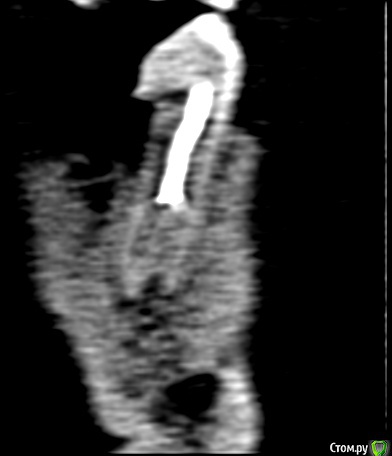

shurkne Опубликовано 1 мая, 2015 Поделиться Опубликовано 1 мая, 2015 (изменено) Здравствуйте!зуб 3.5Полтора года назад лечен резорцином(начал беспокоить...я как понимаю там периодонтитподскажите перелечивать его или удалять? Изменено 1 мая, 2015 пользователем shurkne Ссылка на комментарий

shurkne Опубликовано 13 мая, 2015 Автор Поделиться Опубликовано 13 мая, 2015 Начал перелечивать этот зуб!лечение проводилось под микроскопомврач смог пройти только 1 канал...второй смог пройти на половину(сказал все закаменело..можно перфорацию получить)в проходимый канал положили каласепт на 2 недели или больше Предложение дальнейшего лечениянепроходимый канал запломбировать чем то что замумифицирует каналв проходимый гутаперчу поделитесь вашими мнениями.... Ссылка на комментарий

shurkne Опубликовано 13 мая, 2015 Автор Поделиться Опубликовано 13 мая, 2015 Да он и не болел..... Просто на кт увидел периодонтит и решил довести зуб до ума.... А то потом бы заболел) Ссылка на комментарий